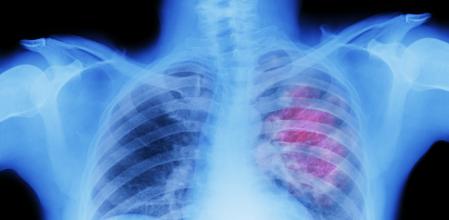

Un tratamiento de inmunoterapia después de la cirugía para extirpar un cáncer de pulmón reduce de manera significativa el riesgo de aparición de un nuevo tumor en los años siguientes, según un ensayo clínico realizado en 227 centros médicos de 22 países y coordinado por el Instituto de Oncología de Vall d’Hebron (VHIO).

El estudio se ha centrado en pacientes con el tipo más común de cáncer de pulmón, llamado no microcítico (o de células no pequeñas), que representa más del 80% de todos los casos de la enfermedad. Los fármacos de inmunoterapia ya se han ensayado con éxito y se utilizan habitualmente en pacientes que son diagnosticados cuando el cáncer de pulmón ya ha causado metástasis. Pero hasta ahora no se había comprobado su eficacia en pacientes diagnosticados en fases más precoces de la enfermedad.

La investigación se ha centrado en el tipo más común de cáncer de pulmón, que representa más del 80% de los casos